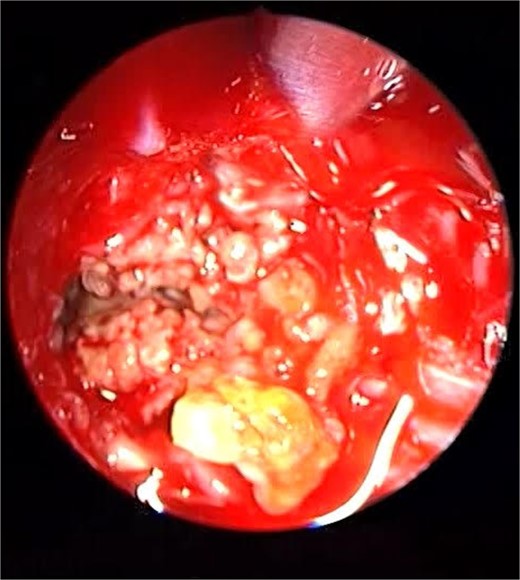

Endoscopic intraoperative view of the sphenoid sinus full of fungal mud and mucin.

Patient presented to the emergency department with four days history of sever left side headache associated with nausea and vomiting, and nasal discharge with on\off nasal obstruction. Two days history of diplopia with lateral gaze of the left eye, with decrease the visual acuity. Ophthalmologic examination revealed left abducens nerve palsy. Other neurologic examinations were within normal. Endoscopic nasal examination revealed left multiple grade two nasal polyps occupying the middle meatus. Pre-operative brain computed tomography (CT) shows bilateral near total opacification and expansion of the paranasal sinuses and nasal cavity (Fig. 1). Additionally, there is evidence of invasion of the left cavernous sinus with encasement of cavernous segment of left internal carotid artery (ICA). Furthermore, pituitary gland and optic chiasm displaced superiorly. Magnetic resonance imaging revealed that the sphenoid sinus is expanded and bulging superiorly into the pituitary fossa causing displacement of pituitary gland and stalk without mass effect upon the optic chiasm (Fig. 2). It extends laterally causing effacement of the cavernous sinus and left Meckel’s cave. No evidence of intracranial extension. The patient underwent functional endoscopic sinus surgery with computer-assisted navigation system. Intraoperatively, sphenoid sinus was full of fungal mud and mucin (Fig. 3). The polyps were removed completely from the nasal cavities, fungal mud, and mucin were removed from the sinuses (Figs 4 and 5). Patient had dramatic improvement after surgery, the rhinosinusitis symptoms are resolved, the diplopia has been improved, and the paranasal sinuses were clear. The patient was discharged with topical corticosteroid and saline irrigations.